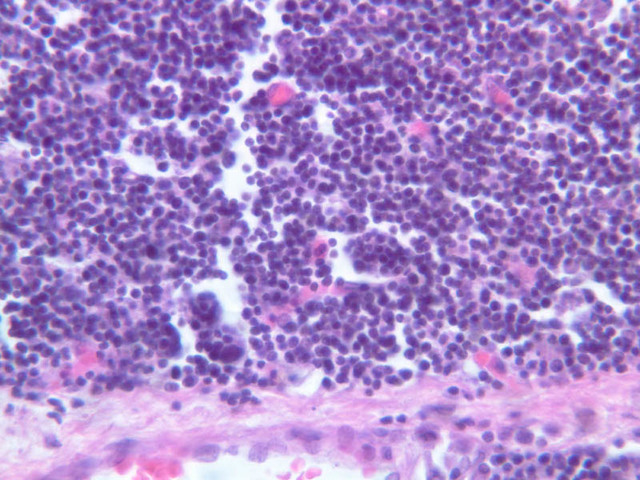

Diffuse Lymphatic Tissue and Nodules

The visceral walls have concentrations of lymphoid tissues that comprise the body's filters against foreign organisms that attempt to enter by way of the alimentary, urinary, or respiratory tracts. The lamina propria is a layer of connective tissue underlying the epithelium of mucous membranes; lymphatic tissue is often found in the lamina propria. This lymphatic tissue can assume three forms; 1) diffuse lymphatic tissue, 2) solitary lymphatic nodules, and 3) aggregated lymphatic nodules. The simplest arrangement of lymphoid tissue occurs as diffuse patches of lymphocytes scattered in the lamina propria of the walls of visceral organs. When a patch becomes activated by antigens or foreign organisms, it takes on the appearance similar to a nodule in the cortex of a lymph node (see below). These nodules are not encapsulated and simply occur in the visceral wall as an accumulation of lymphocytes, macrophages, and plasma cells embedded in reticular tissue. Eosinophilic leukocytes are frequently seen.

In lymphatic nodules and nodes the term primary nodule refers to a nodule of homogeneously, tightly packed small lymphocytes. When lymphatic nodules have germinal centers they are called secondary nodules. A germinal center contains lighter staining, "B" lymphocyte precursors. Mitotic figures should be easily spotted in the core of the nodule. Compare these cells with the mass of small more differentiated lymphocytes that surround the germinal center. Some of these lymphocytes are cytokine producing T-Helper cells that are stimulating the proliferation of the lymphoblasts.